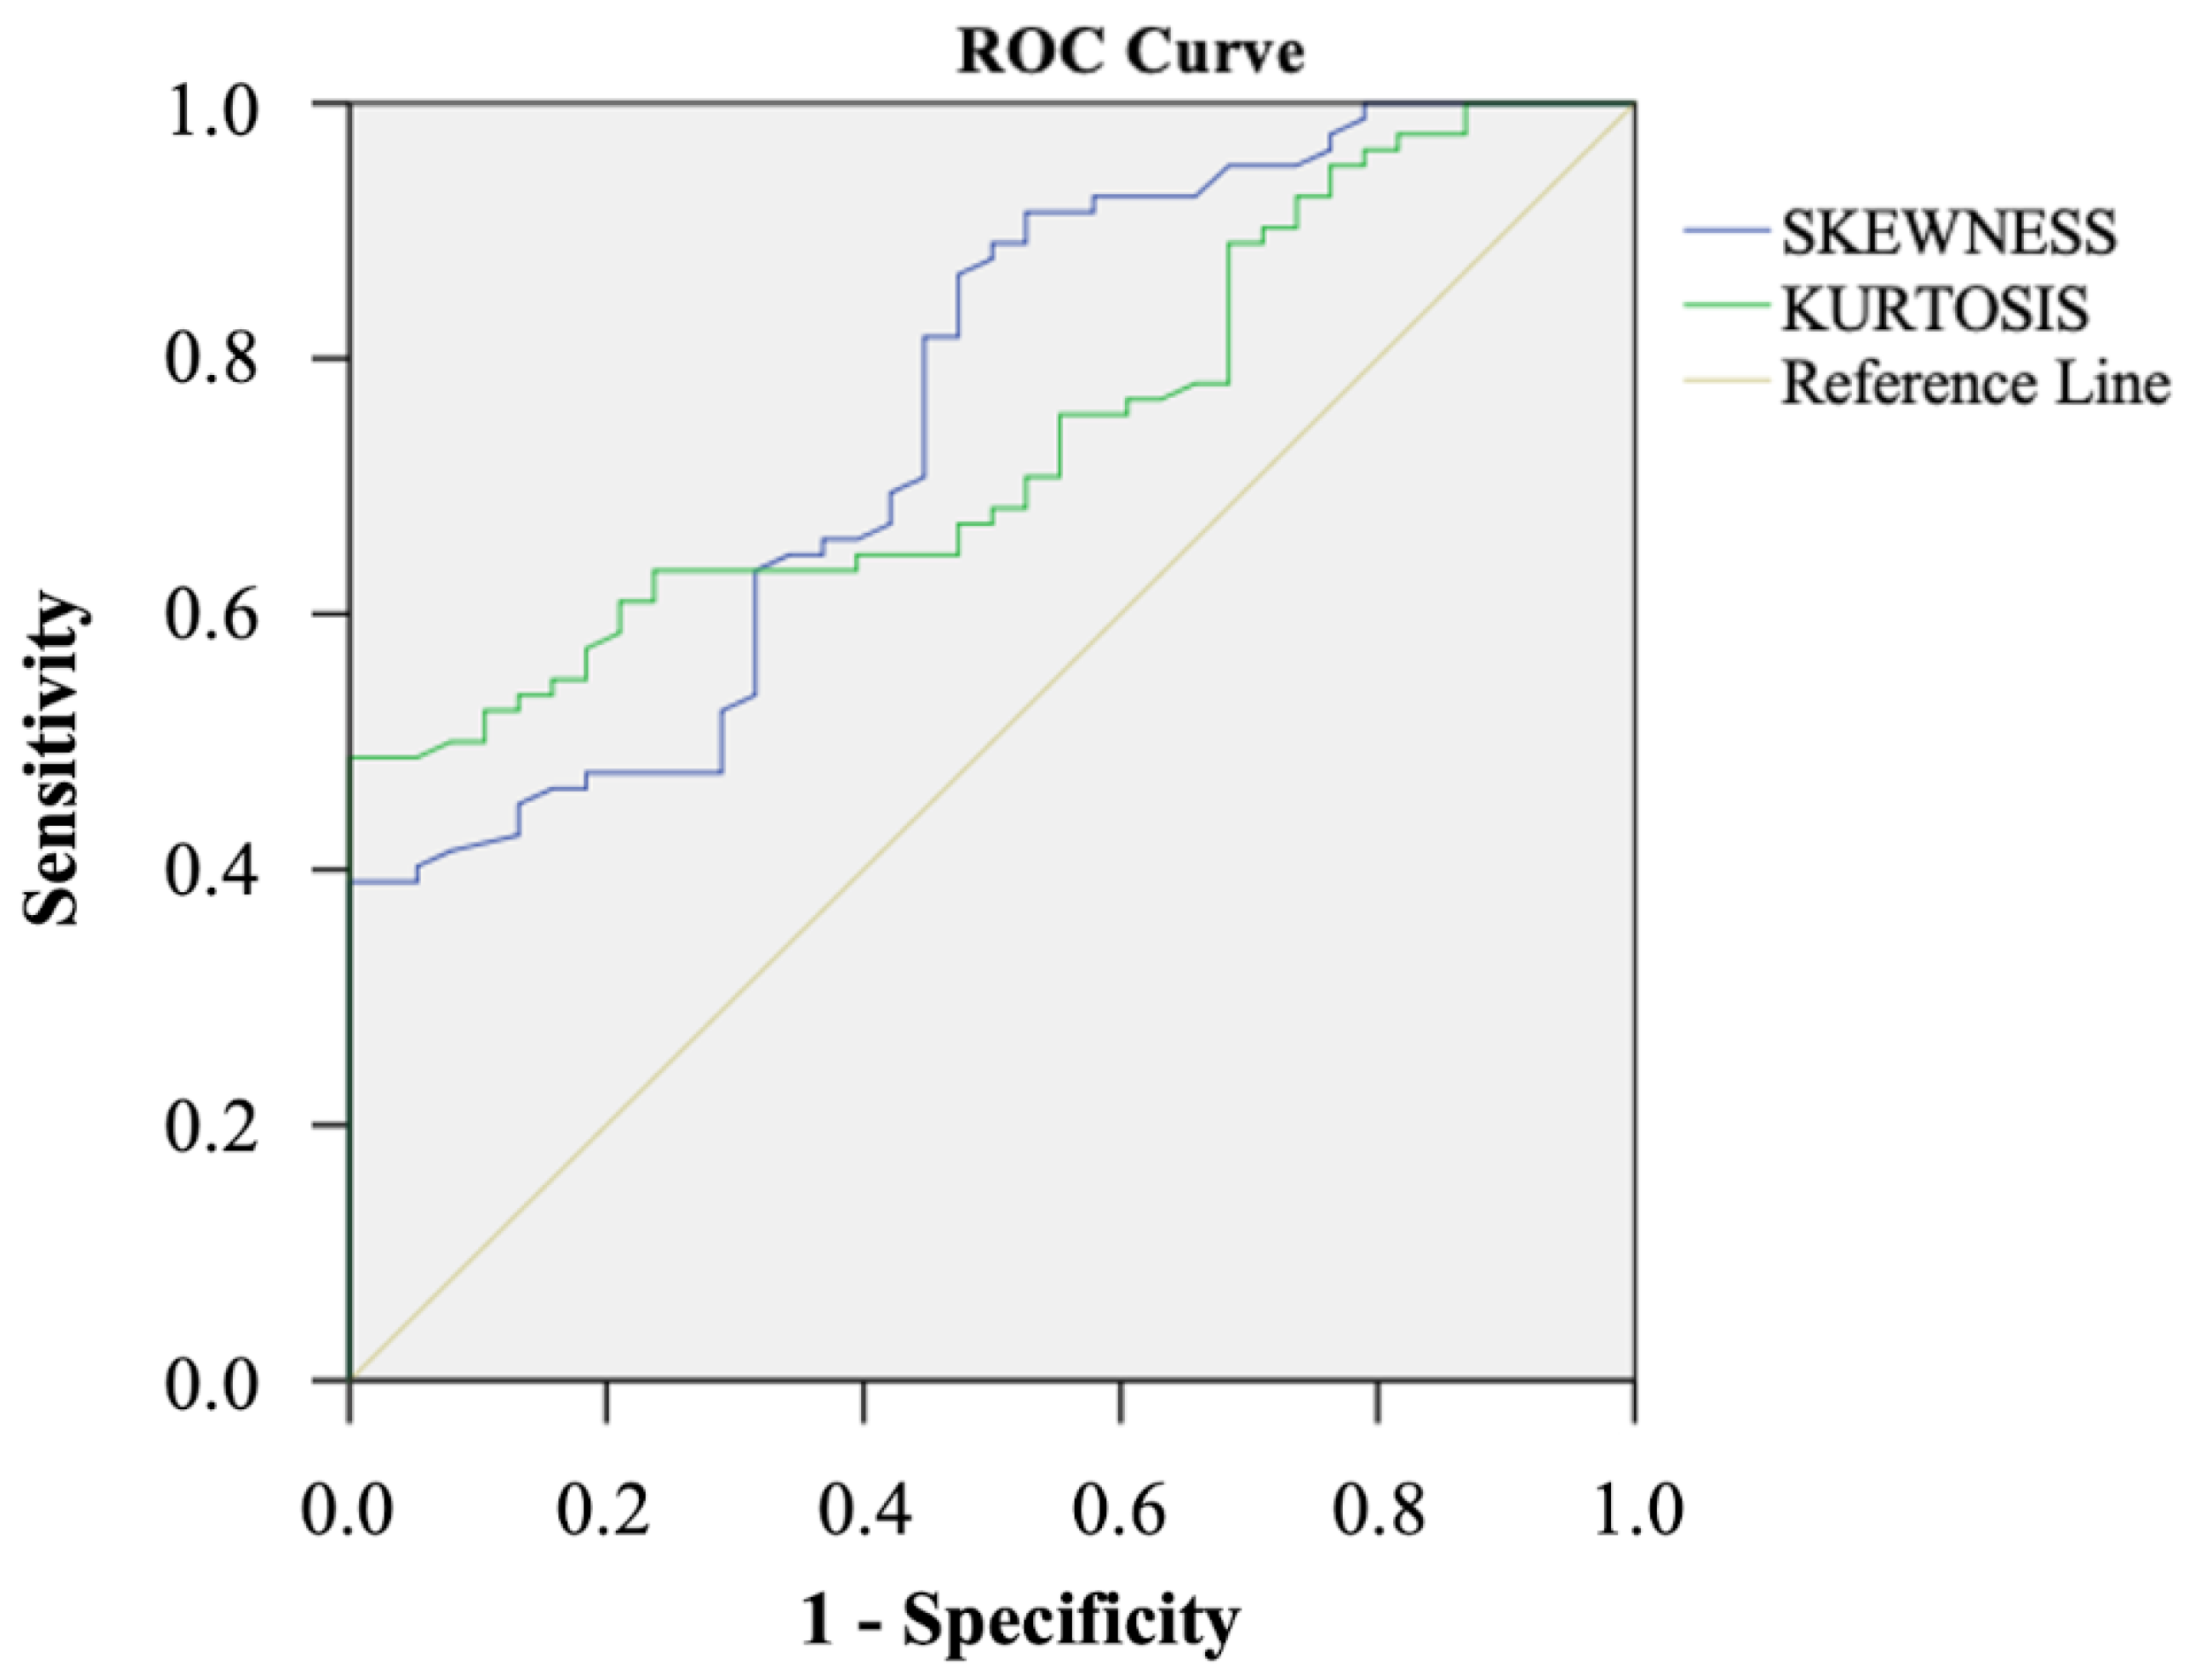

| Skewness | 0.6 (−0.6;3.3) | 0.2 (−1.2;1.8) | 0.005 |

| Kurtosis | 4.3 (1.7; 17.3) | 3.8 (2.1; 11.1) | 0.032 |

| ADC Skewness | ADC Kurtosis | |

|---|---|---|

| Optimal Cut-off | 0.23 | 3.90 |

| Sensitivity | 98.6 (92.5–100) | 47.6 (36.4–58.9) |

| Specificity | 41.7 (27.6–56.8) | 100 (91–100) |

| PPV | 71.7 (66.6–76.3) | 100 (-) |

| NPV | 95.2 (73.5–99.3) | 46.9 (41.8–52.1) |

| Accuracy | 75.8 (67.2–83.2) | 64.2 (54.9–72.7) |